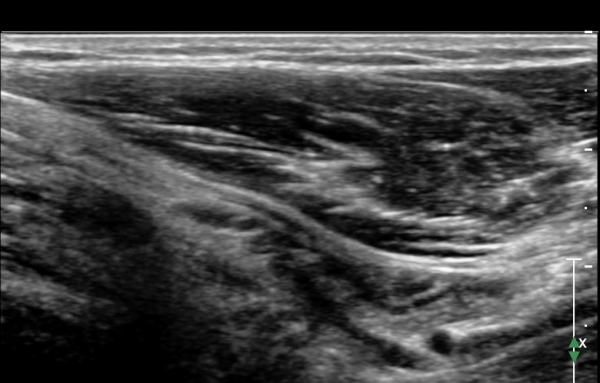

ÃÊÀ½ÆÄ °Ë»ç : ȸ³»±Ù ±ÙÀ§ºÎ¿¡¼ Á¤Á߽Űæ Ⱦ´Ü¸é°Å»ç¿¡¼ ƯÀÌ ¼Ò°ßÀ» º¸ÀÌÁö ¾ÊÀ¸³ª(»çÁø 1) ȸ³»±Ù ¿ä°ñµÎ ±â½ÃºÎ ¿¡¼ Á¤Á߽ŰæÀÇ ±¹°íÀû ¾Ð¹Ú ¹× ÆíÆòȰ¡ °üÂûµÊ(»çÁø 2). ÀÌ·± º¯È´Â °ÇÃø(»çÁø 5)°ú ºñ±³ÇÏ¸é ¶Ñ·ÇÇÔ.

Á¤Á߽Űæ Á¾´Ü¸é°Ë»ç¿¡¼ ȸ³»±Ù ¿ä°ñµÎ ±â½ÃºÎ¿¡¼ Á¤Á߽ŰæÀÇ ±¹¼ÒÀû ¾Ð¹Ú°ú Ç¥ÃþÀ¸·Î ÀüÀ§°¡ °üÂûµÇ°í ¾Ð¹ÚÀÇ ±ÙÀ§ºÎ¿¡¼´Â Á¤Áß½Å°æ ºÎÁ¾ÀÌ °üÂûµÊ(»çÁö 3). ÀÌ·± º¯È´Â °ÇÃø(»çÁø 6)°ú ºñ±³ÇÏ¸ç ¶Ñ·ÇÇÔ.